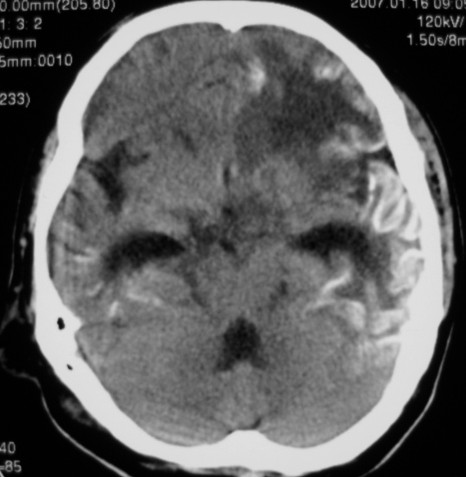

标题: CT9218:男性,50岁,脑出血术后复查,两次片相隔半月,请分 [打印本页]

标题: CT9218:男性,50岁,脑出血术后复查,两次片相隔半月,请分

第一次ct片脑出血术后,出血吸收期。第二次ct 片左颞顶枕部及右颞顶部有脑回样高密度影。考虑珠网膜下腔出血。脑出血术后改变,脑出血恢复期 并脑积水。

是蛛网膜下腔出血么?蛛网膜下腔出血应该在脑沟里,而此高密度影是沿脑回分布,应该是脑膜感染后钙化灶形成。

脑回状高密度影,首先要考虑脑颜面血管瘤病,不知高密度区ct值多少,对于鉴别是蛛网膜下腔出血还是钙化有意义,只是病人半月前“钙化”还较局限,因此还是考虑与脑出血有关。当然要密切结合病史及临床,增强扫描有意义。

两次的片都有,第二次比第一次的明显